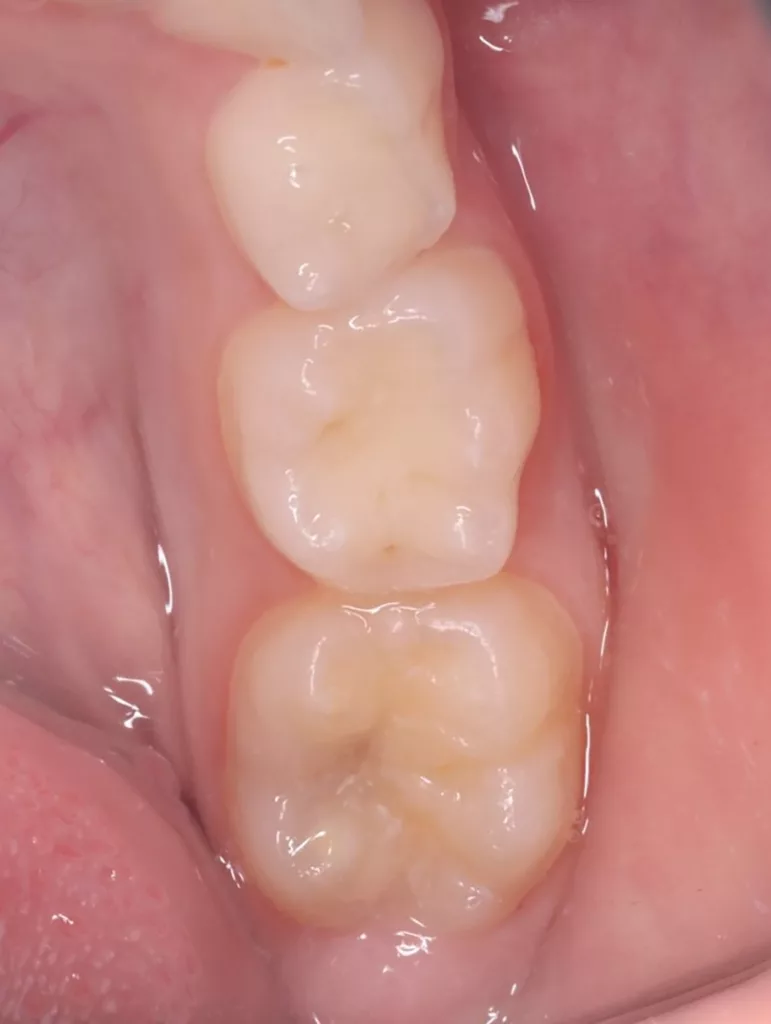

Das fünfjährige Mädchen stellte sich 2017 zur jährlichen Routinekontrolle vor. Im Rahmen der Untersuchung wurden Röntgenaufnahmen der Milchmolaren gemacht (Abb. 2). Der klinische und radiologische Befund der vor uns früher gelegten Kompositfüllungen war gut, es wurde allerdings eine PEIR an den noch nicht durchgebrochenen ersten bleibenden Molaren festgestellt (Abb. 2). Den Eltern wurde empfohlen, sich unverzüglich bei Beginn des Durchbruchs der ersten Molaren erneut zur Behandlung vorzustellen. Ein Jahr später erschien die junge Patientin schmerzfrei zur Kontrolle. Der Zahn 36 war noch teilweise mit Gingiva bedeckt. Auf einer neuen Röntgenaufnahme (Abb. 1) wurde die PEIR-Läsion mit unveränderter Größe in pulpanahen Bereichen bestätigt (Grad 3 der Läsion nach Seow). Der Zahnschmelz sah intakt aus, es konnte kein pathologischer periapikaler Befund bei den noch nicht ausgewachsenen Zahnwurzeln festgestellt werden. Daraufhin wurden die verschiedenen Behandlungsmöglichkeiten von Fissurenversiegelung bis Vitalerhaltung der Zahnpulpa mit den Eltern des Kindes besprochen.